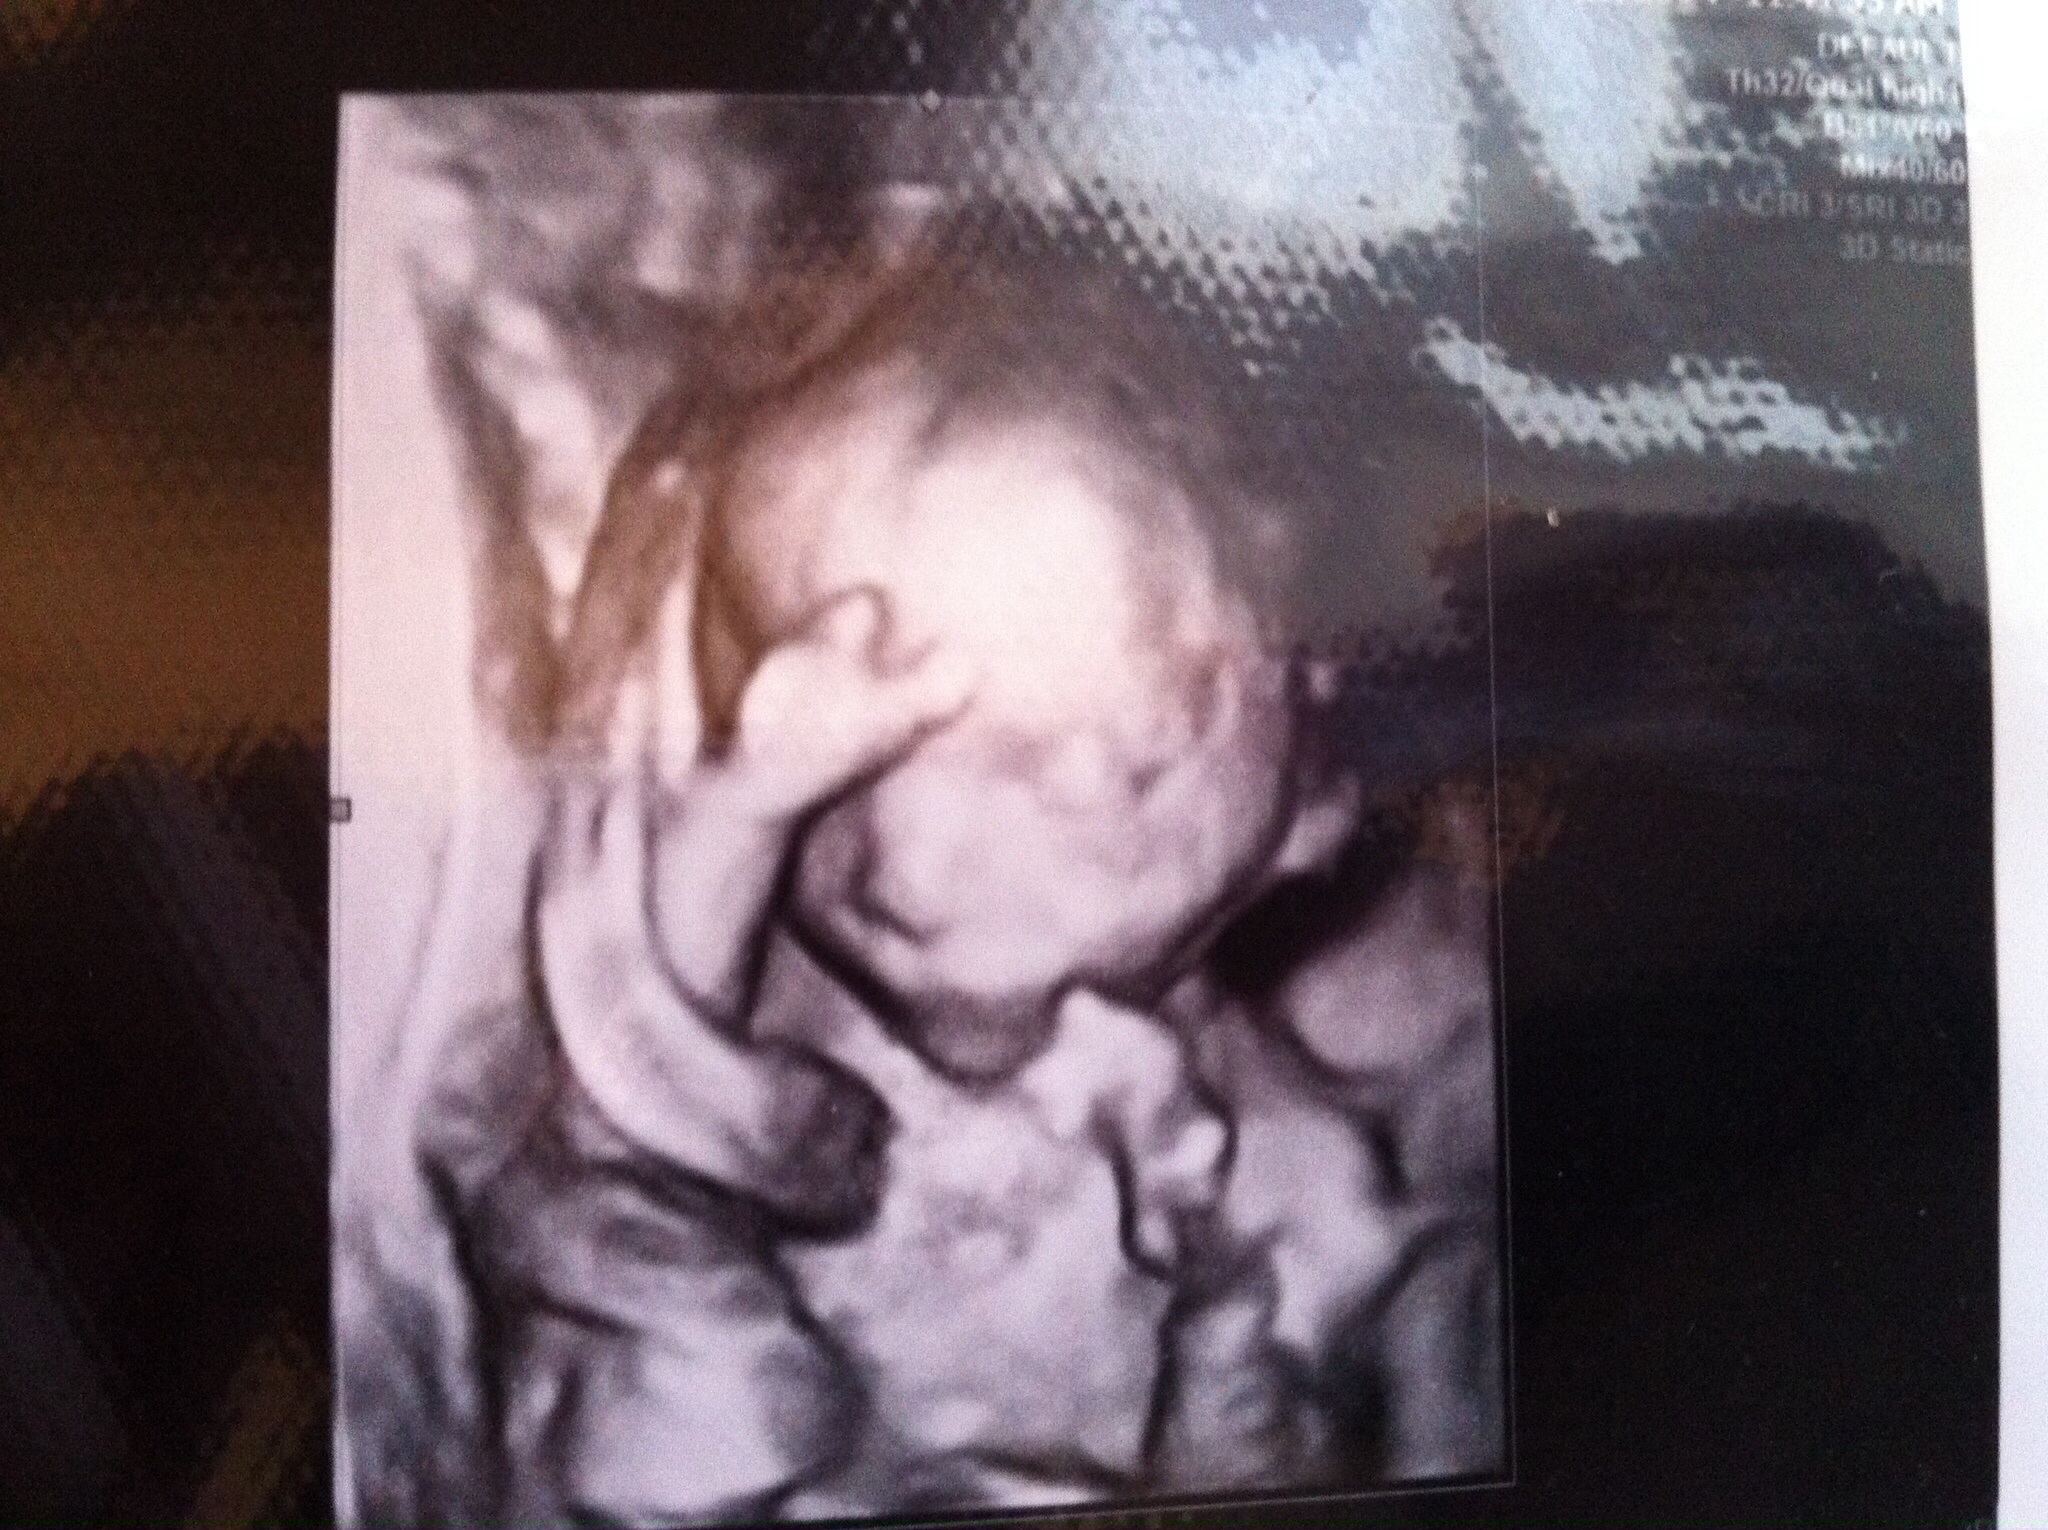

Share your fav pics of your LO here!!! :)